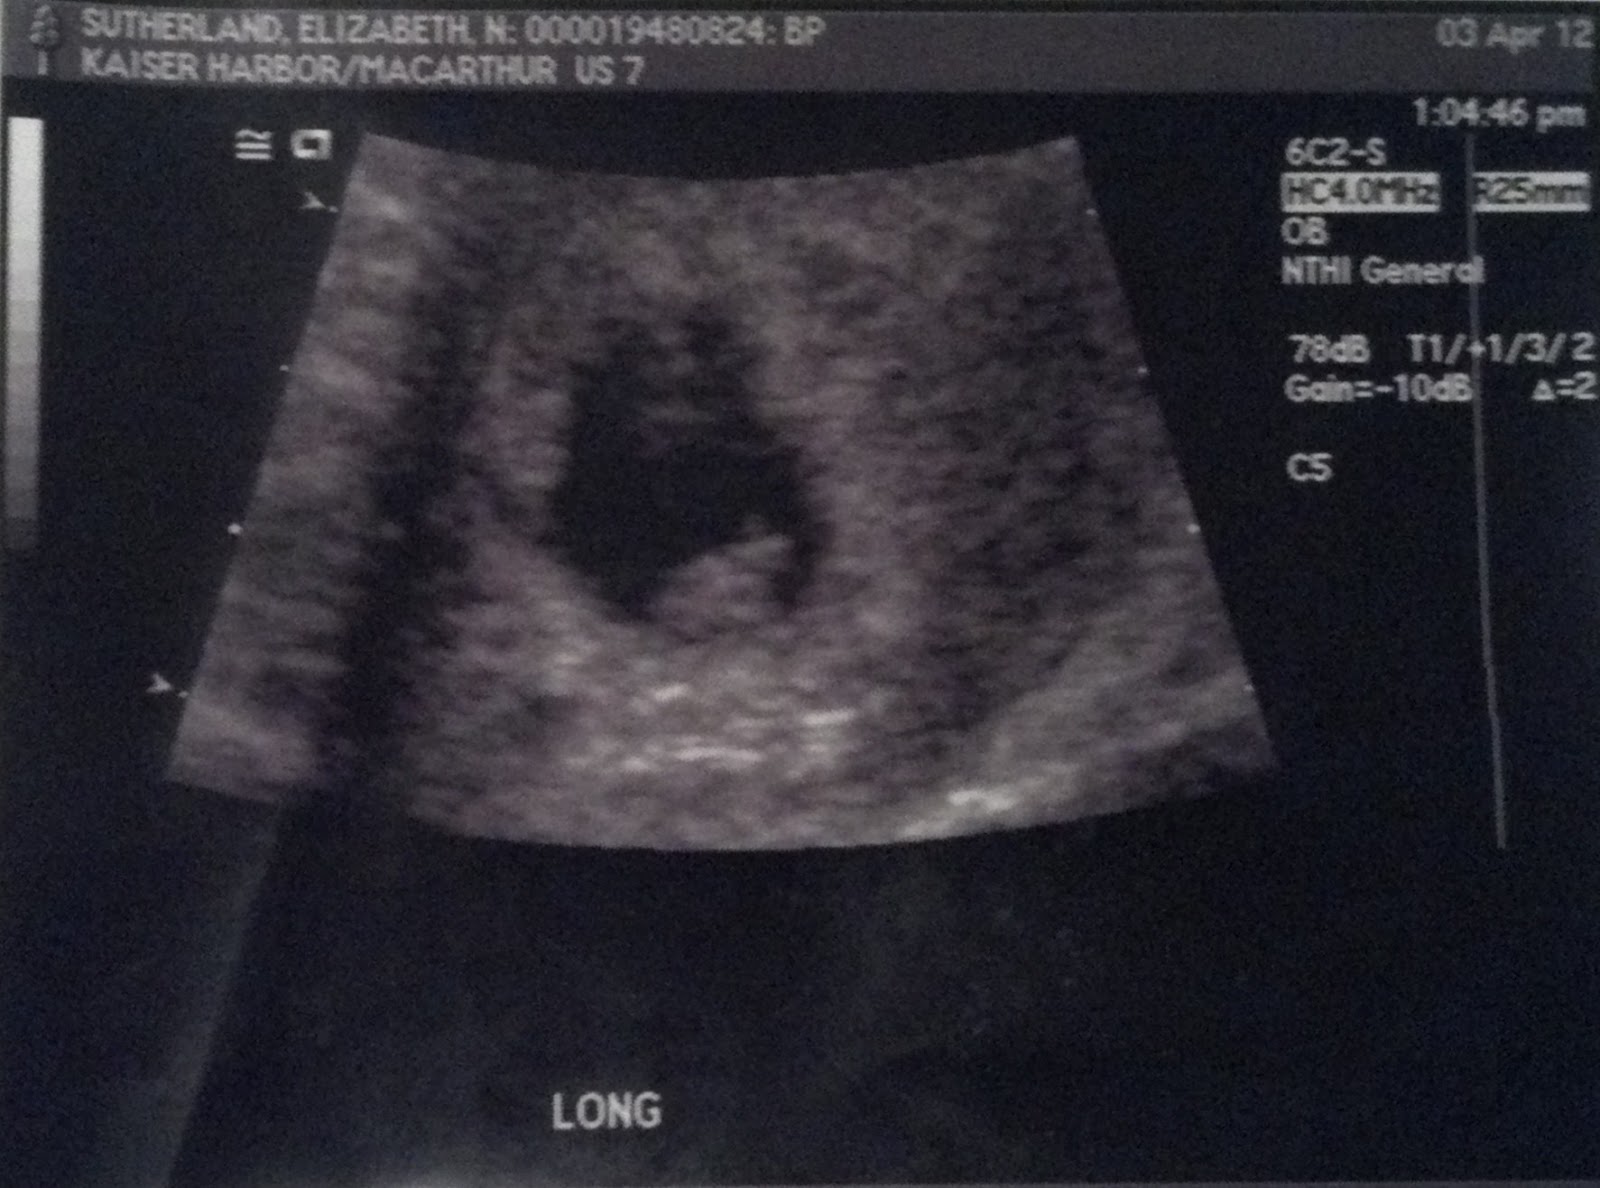

Wednesday, April 4, 2012

heartbeat!

so much has happened today! i got my first picture of you, and heard your little heartbeat!

your only 7w1d, and so teeny tiny! your feet and hands are growing this week. i cant wait to see you again!

next ultrasound appointment isn't until your 18 weeks. i cant wait for that one, then i will know if you are a baby girl or baby boy!

so 11 weeks to go!

the size of a blueberry! your growing so fast <3